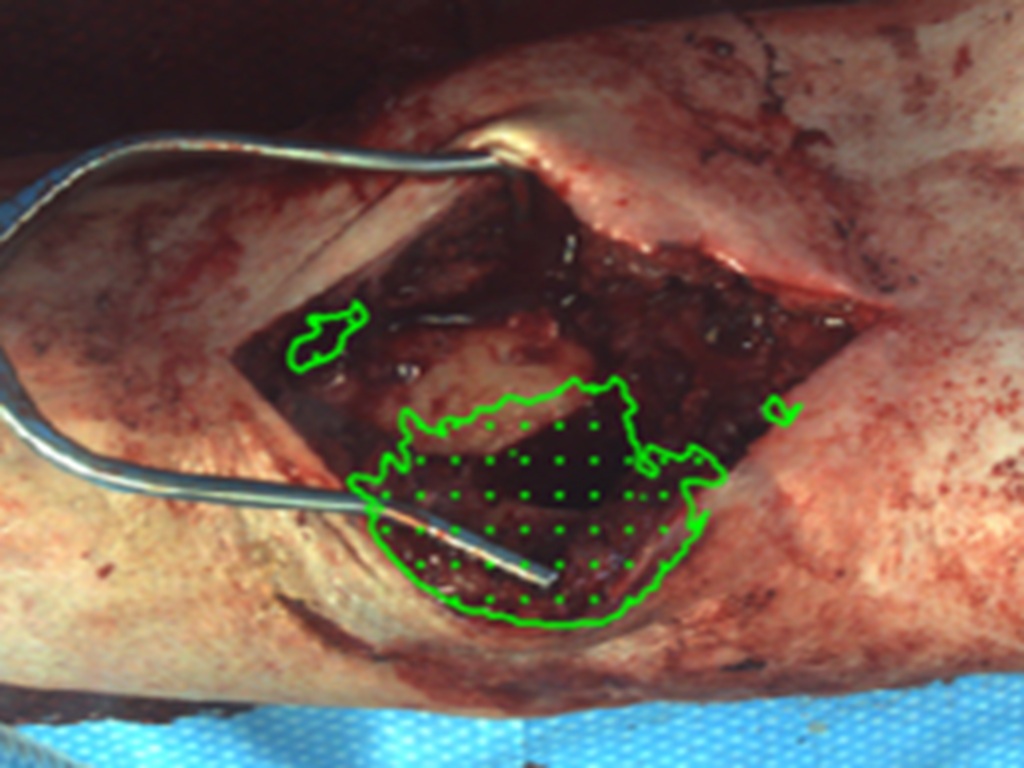

Fluorescence Guided Debridement (FGD) is a surgical method that uses a special dye, given through an IV, to help surgeons see better during debridement. A light shines on the surgical area, showing how the dye moves through bone and tissue, helping surgeons spot and remove dead tissue more accurately. This can lower the chance of infection and improve healing for patients.

Our algorithm takes fluorescence video and converts it to an actionable debridement plan. Move the slider below to view.

FGD has the potential to decrease infection by up to 50% in certain patients undergoing debridement. In a clinical trial of 110 patients (NCT04403204), a large amount of retained low-perfusion tissue was associated with a 29% recurrence rate after 6 months compared with 12% when a small amount was retained. Information obtained with this device will be used by the surgeon to make better informed debridement decisions, to optimize the amount of debrided tissue.